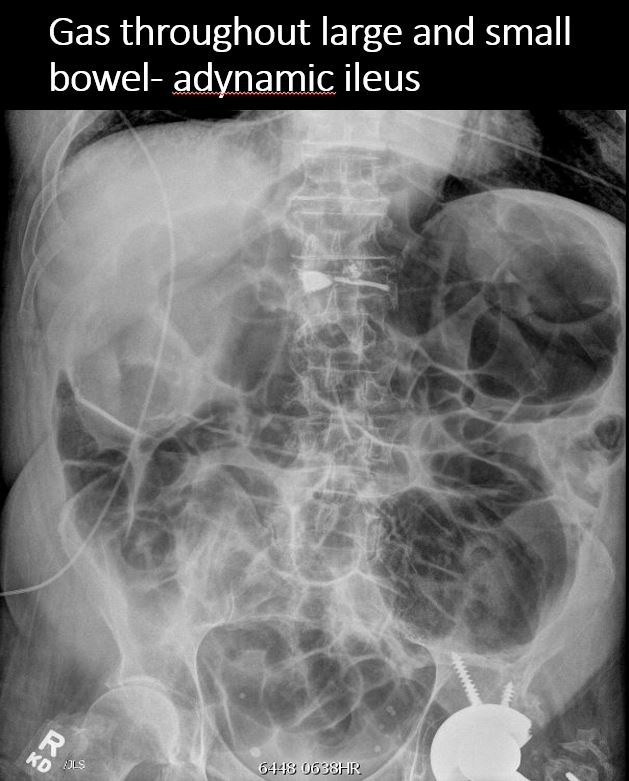

Section 1 Submit Findings CB1518 Findings Scout Image of the abdomen There is an NG/OG/FT tube which is malpositioned Yes No There is an unexpected radiopaque foreign body or incidental non-surgical foreign body in the abdomen or pelvis. Yes No There are additional lines, tubes, catheters or drains in place (examples include chest tubes, mediastinal drains, rectal temperature probe, etc.). Yes No There is dilatation with gas or fluid of multiple or diffuse loops of bowel. Yes No ​Both the small and large bowel are filled with air and/or fluid and may or may not be distended. Yes No There is a paucity of gas in the abdomen. Yes No There are centralized loops of small bowel with distention of the abdomen and pelvis. Yes No There is organomegaly. Yes No There are intra-abdominal calcifications. Yes No There is free air present. Yes No The visualized bones are abnormal. Yes No Fluoroscopic examination of the chest shows pneumonia, atelectasis, or cardiomegaly. Yes No The hemidiaphragmatic excursions are inequal and nonsynchronous. Yes No Procedural The patient was given thin barium/water soluble contrast to drink via bottle/syringe/sippy cup/straw/cup. A total of---mL of thin barium/water soluble was used for this examination. Yes No The exam is limited by patient motion or non-cooperativity. Yes No The exam is limited by small or inadequate boluses/contrast intake. Yes No The swallowing act is abnormal. Yes No There is tracheal aspiration. Yes No The course of the esophagus is abnormal. Yes No The caliber of the esophagus is abnormal. Yes No There is stenosis of the upper/mid/distal esophagus. Yes No There is dilatation of the upper/mid/distal esophagus. Yes No There is a tracheoesophageal fistula present. Yes No There is a filling defect. Yes No There is dysmotility of the esophagus. Yes No There is extrinsic mass effect. Yes No There is a vascular ring. Yes No The stomach does not fill readily. Yes No If the contrast is instilled via NG tube/gastrostomy tube/orogastric tube: There is abnormal contrast opacification of the stomach. Yes No The stomach empties abnormally. Yes No There is gastric outlet obstruction. Yes No The duodenal C-loop is abnormal in size. Yes No The location of the ligament of Treitz is abnormal. Yes No The proximal jejunum is dilated. Yes No There is gastroesophageal reflux observed to the upper/mid/distal esophagus. Yes No The reflux does not clear quickly. Yes No N/A